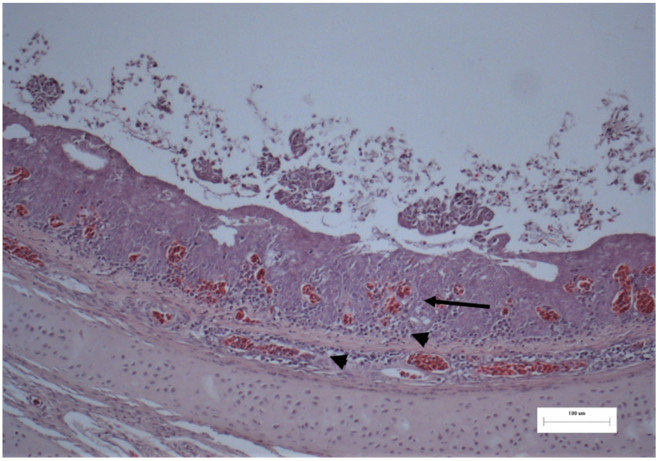

2.4. Histopathological Examination